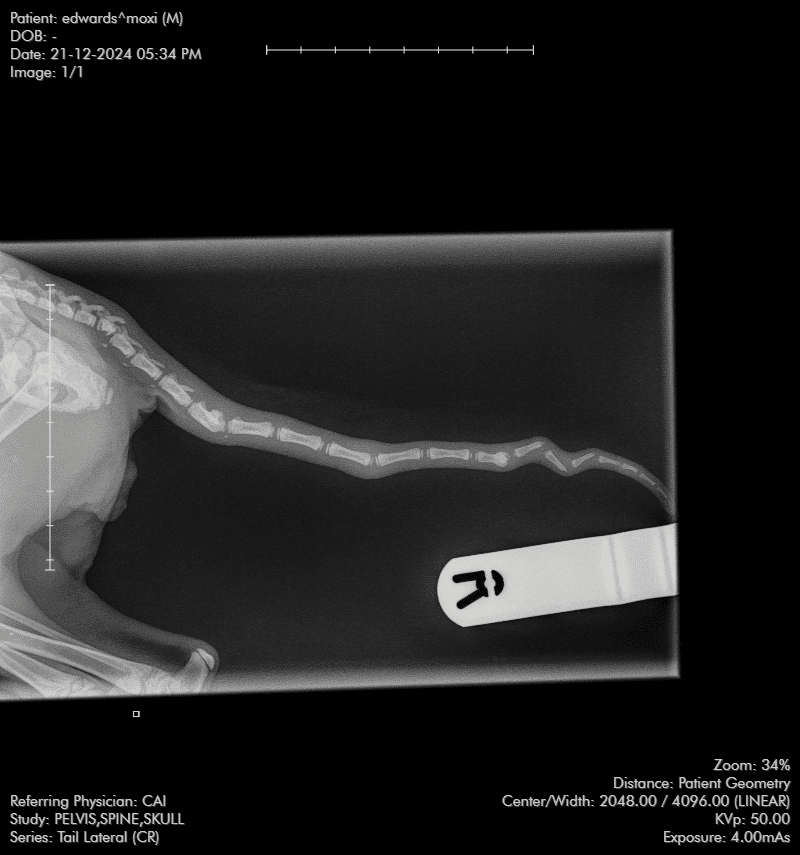

The court heard how the RSPCA started an investigation after Inspector Simon Evans attended the PDSA clinic in Cardiff on December 24, 2024 when he was shown the four-month-old tabby kitten which Edwards had brought in four days earlier. X-rays showed the feline had bony damage to the front of his skull and there were a number of older fractures/dislocations to his tail. The kitten’s lip was split and there was an injury to the right eye along with swollen genitalia.